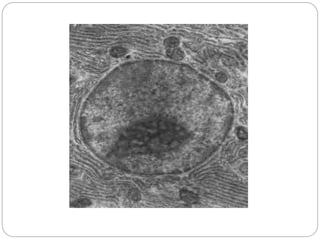

1. Unsur kehidupan terkecil adalah sel

2. Satu sel merupakan kehidupan mandiri atau bagian dari kehidupan

yang lebih kompleks

Sel

Jaringan

Sistema

Organ

Organisme

Derajat kesehatan sel menentukan kualitas

fungsionalnya sehinga akan menentukan derajat

kesehatan, kualitas hidup dan vitalitas individu